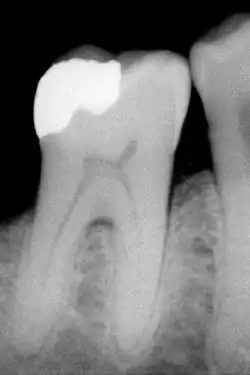

B) Röntgenologische Diagnostik

Die Präsentierung von Karies ist sehr variabel, allerdings sind die Risikofaktoren und Stadien der meisten Erscheinungsbilder identisch. Je nach Lokalisation ist die Karies entweder direkt sichtbar, oder kann erst durch diagnostische Werkzeuge (Röntgen, Sonden, Laser) sichtbar gemacht werden.[11] Die primäre Diagnosestellung beim Zahnarzt erfolgt in erster Linie durch Inspektion mit einer starken Lichtquelle, einem zahnärztlichen Spiegel und einer Sonde in Kombination mit Druckluft. Die Ergebnisse der Inspektion werden mit Röntgenbildern verglichen, die Karies in den nicht-zugänglichen Bereichen der Zähne (Fissuren, Kontaktpunkte zwischen den Zähnen) sichtbar machen können. Hierzu werden Bissflügelaufnahmen angefertigt.[12] Der Einsatz von Sonden zur Kariesdiagnose, insbesondere solcher mit spitzen Enden, wird in der Fachliteratur kontrovers diskutiert.[13] Karies im frühen Stadium kann durch den Einsatz von Fluoriden gestoppt werden, solange sich noch keine Kavität gebildet hat. Solche Bereiche könnten durch spitze Sonden einbrechen, wodurch die erkrankte Stelle nicht mehr allein durch Fluoridierung remineralisiert werden kann.[14]